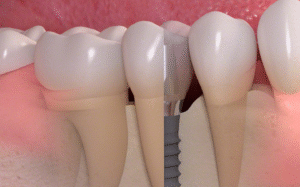

Процедура имплантации зубов в Туле: все, что вам нужно знать

Думаете об имплантации зубов? Отличный выбор! Здесь мы подробно рассказывается о том, что такое имплантаты и как они работают, о восстановлении, материалах и рисках. Потеря зуба может быть неприятным испытанием не только для вашей улыбки, но и для приёма пищи, речи и уверенности в себе. Именно здесь на помощь приходят зубные имплантаты! Зубные имплантаты — …

Имплантация зубов: путь к восстановлению улыбки и уверенности

Имплантация зубов – это современный и эффективный способ восстановления утраченных зубов. Этот метод позволяет не только вернуть эстетику улыбки, но и восстановить функциональность зубного ряда, улучшить качество жизни. Больше информации можно узнать на сайте https://factorsmile.ru/uslugi/implantatsiya/. Что такое имплантация зубов? Имплантация зубов – это хирургическая процедура, в ходе которой в костную ткань челюсти вживляется титановый имплантат, …

Имплантация зубов: современные методы восстановления улыбки

Имплантация зубов – это современный и эффективный способ восстановления зубного ряда, который позволяет вернуть не только эстетическую привлекательность улыбки, но и полноценную функциональность зубов. Как выбрать метод имплантации зубов, мы подробно рассмотрим в этой статье, чтобы вы могли сделать осознанный выбор в пользу здоровья и красоты вашей улыбки. Что такое имплантация зубов? Имплантация зубов – …